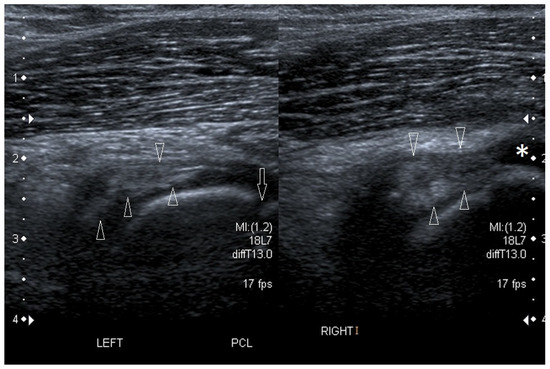

We present basic differences in the musculoskeletal ultrasound examinations between adults and children. Examiners who deal with adults on a daily basis have shared concerns about examining children. Such concerns may arise from the different approach to child ultrasounds, but they also come [...] Read more.

We present basic differences in the musculoskeletal ultrasound examinations between adults and children. Examiners who deal with adults on a daily basis have shared concerns about examining children. Such concerns may arise from the different approach to child ultrasounds, but they also come from differences in anatomical characteristics according to developmental age. We discuss the presence of growth plates, as well as non-mineralized parts of the bones. We also refer to the pathologies most often found in ultrasounds in early developmental stages. In the PubMed database, the set of keywords: “msk ultrasound in children”, “pediatric msk sonoanatomy”, “coxitis fugax”, “pediatric Baker’s cyst”, “Baker’s cyst ultrasonography”, “bone septic necrosis in ultrasonography”, “ultrasonography in juvenile idiopathic arthritis”, and “ultrasonography in juvenile spondyloarthropathies”, was used to identify a total of 1657 results, from which 54 was selected to be included in the article. We discuss the problem of osteochondritis dissecans, Osgood-Schlatter disease, examples of ligament injuries (especially in relation to the knee and ankle joints), exfoliation of growth cartilages, osteochondroma, exudates and inflammations affecting joints, and Baker’s cysts. In this way, we have collected useful information about the most common diseases of the musculoskeletal system in children. Full article